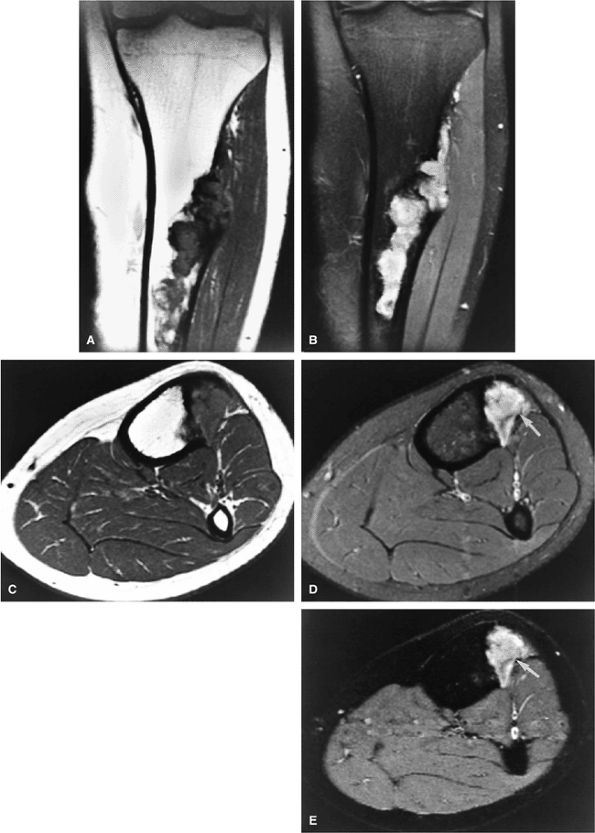

FIGURE 14-73 ● Parosteal osteosarcoma. Anterior coronal (A) and axial (B) T1-weighted images show a large lobulated mass of low signal intensity arising from the metadiaphyseal surface of the tibia (arrows). Tumor is hyperintense on sagittal (C) and axial (D) fat-suppressed T2-weighted fast spin-echo images. Tumor enhancement is noted on axial fat-suppressed T1-weighted image (E) following administration of intravenous gadolinium.